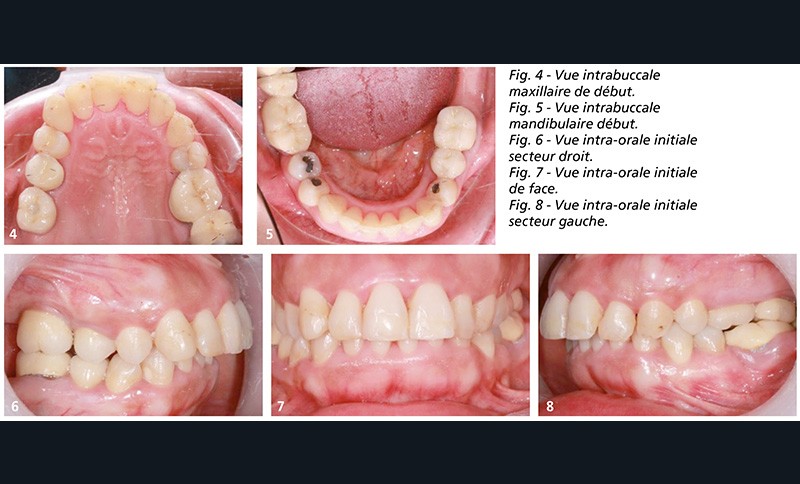

À l’examen endobuccal (fig. 4 à 8), elle présentait une arcade dissymétrique avec absence de 17, 18, 25, 28, 36, 47, 48, un implant en 16, des couronnes solidarisées sur 26-27 et 47-48 (lesquelles par la taille de la couronne remplaçaient partiellement la 46), des couronnes sur 15 et 16 ainsi que plusieurs soins.